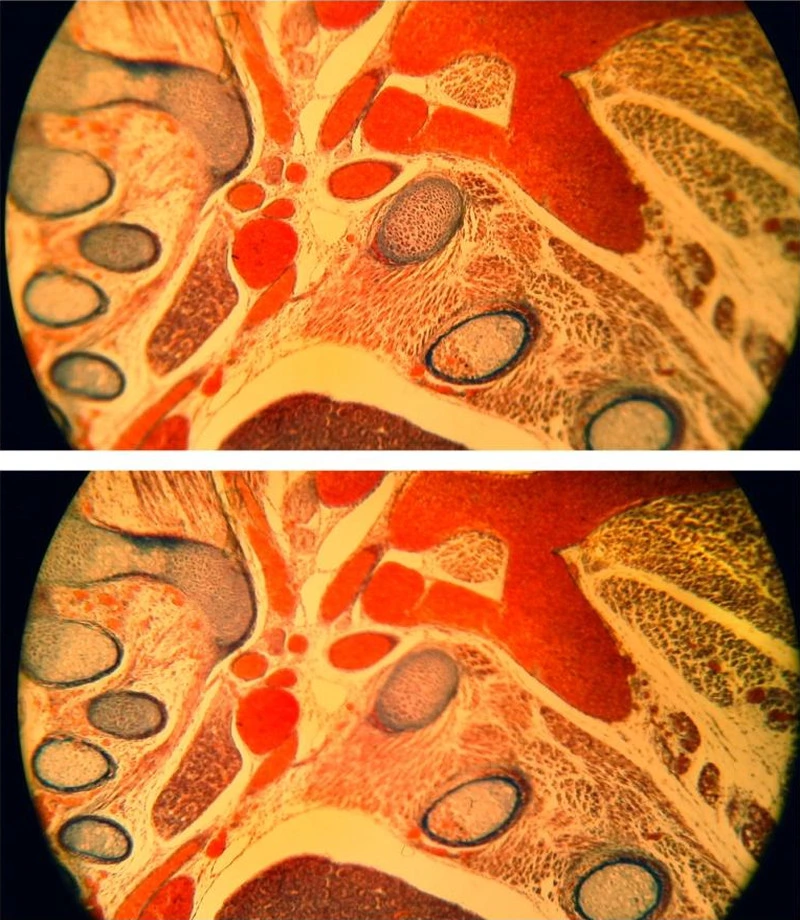

在这种情况下,具有明显边缘柔化的非平面校正物镜(简易的消色差物镜)可用来进行测试,且显微镜可持续对焦样本,或可选择将自动对焦设定对准观测区域的中心或周围(图 12)。尽管手动调整聚焦面,而不调整焦距,选择性自动对焦仍可让人轻易对周围重新对焦和观测屏幕影像上的任一有趣细节。